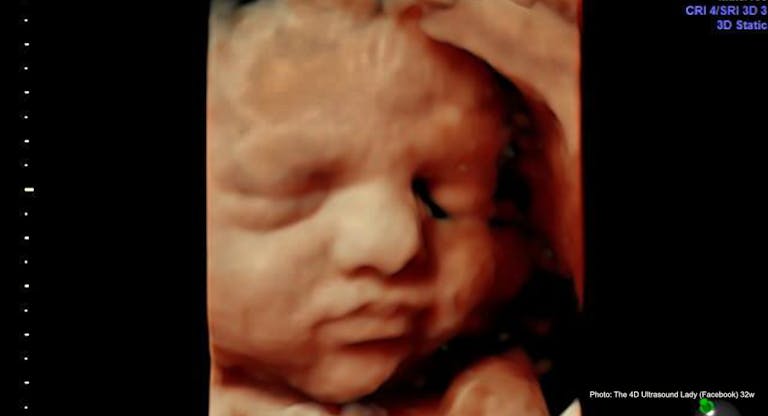

Such a ruling indicates that the decision has less to do with the girl’s health and more to do with her alleged low IQ and the rape. At 33 weeks, her baby has a 95% chance of survival. The only difference between an induction abortion at that stage of pregnancy and an induction delivery is the goal of the procedure. In an induction abortion, the goal is to ensure the baby is dead before delivery, while the goal of induction of labor would be to protect both the baby’s and the mother’s health and life.